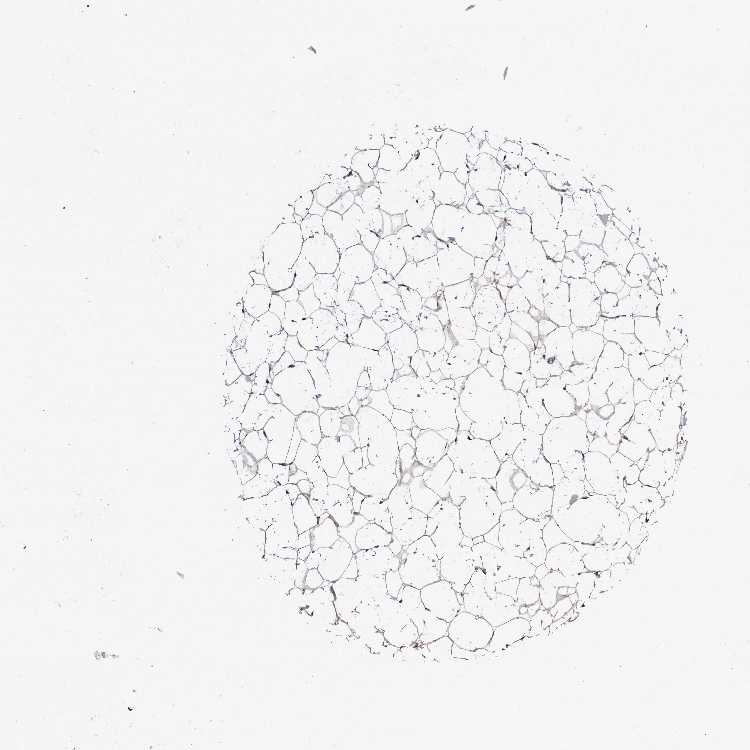

SOFT TISSUE 2 - Antibody stainingi

Antibody staining in the annotated cell types in the current human tissue is reported as not detected, low, medium, or high, based on conventional immunohistochemistry profiling in selected tissues. This score is based on the combination of the staining intensity and fraction of stained cells.

Each image is clickable and will lead to virtual microscopy that enables deeper exploration of all samples and also displays staining intensity scores, fraction scores and subcellular localization as well as patient and tissue information for each sample.

Antibody HPA039535Antibody HPA058867

Chondrocytes Low-

Fibroblasts LowLow

Peripheral nerve LowNot detected